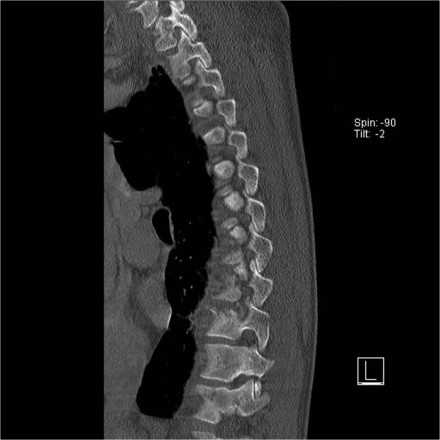

Scroll through the images.

What are the findings?

In this case the main findings are the horizontal fractures of the posterior elements.

The vertebral body fractures show hardly any compression.

Notice that there are 3 vertebrae involved.

Only the level with the highest score counts.

TLICS score based on imaging is 7 points:

- Distraction: 4 points

- PLC involvement: 3 points

In this case there is severe compression of the vertebral body.

However the most important findings are the horizontal fractures of the posterior elements.

TLICS score based on imaging is 7 points.

Scroll through the images.

What are the findings?

The findings are:

- The main feature is posterior distraction with horizontal fractures of posterior elements (red arrow)

- Avulsion of a spinous process (yellow arrow)

- Widening of facet joint (green arrow)

- Burst-type fracture

In this case some would call this a burst fracture with PLC-injury i.e. 2+3 points.

However the distraction is the most important finding, i.e. distraction and PLC injury, i.e. 4+3 points.